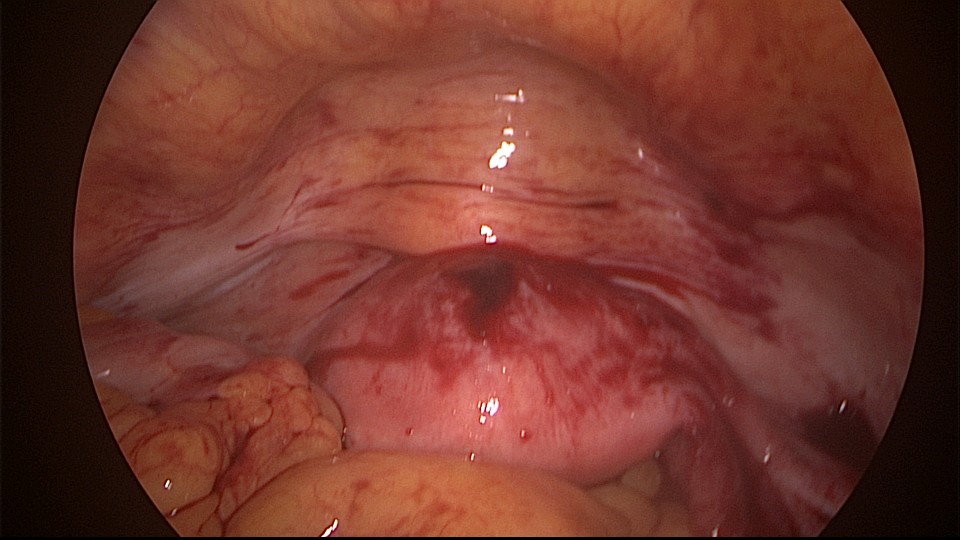

患者54岁,G1P1,顺产1次。安环33年,绝经3年,外院取环失败,子宫穿孔,盆腔积血。子宫后位,宫腔镜见宫颈管组织杂乱,宫颈管上段前壁不规则潜行假道,假道后侧寻找到宫颈内口。扩张宫颈内口,进入宫腔,见O型环位置正常,异物钳取出节育环,宫腔内看不到子宫穿孔。腹腔镜见盆腔积血约400ml,子宫前壁中段偏左见直径0.5cm不规则穿孔,少许渗血,缝合修补子宫穿孔。因左侧卵巢囊肿,患者及家属要求切除双侧附件。